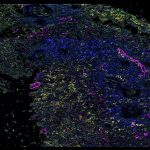

- IBEX uses antibodies so that HuBMAP researchers like Dr. Andrea Radtke at Germain lab can see cellular differences between healthy and tumor cells in lymph nodes. This is an image of follicular lymphoma lymph node showing stromal remodeling, a-SMA (orange) and SPARC (cyan), around B cell follicles (purple). a-SMA (orange) labels fibroblasts, CD20 (purple) labels B cells, SPARC (cyan) labels macrophages, stroma, matrix interactions.